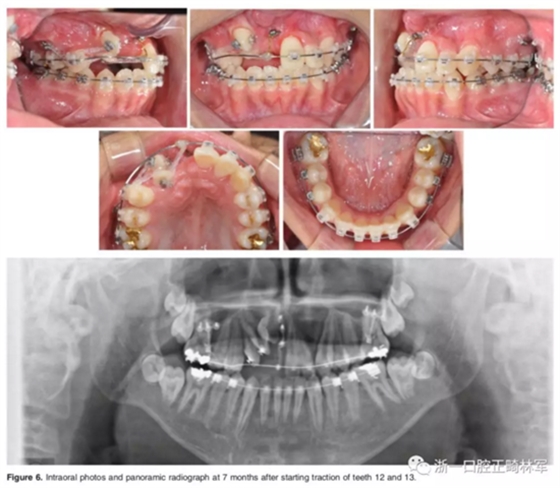

一期手術主要是牽引側切牙和尖牙:于上頜前牙區(qū)唇側作切口,翻全厚瓣;腭側面較小;在尖牙唇側、側切牙腭側粘扣掛結扎絲牽引,通過一輔助鈦板及樹脂等連接至弓絲上;采用閉合式導萌技術,將皮瓣復位縫合,僅結扎絲穿過粘膜;2周內軟組織得以愈合,牽引開始。先通過正畸力,近中移動側切牙,遠中移動尖牙。10個月后,阻生牙牙冠萌出,側切牙、尖牙的易位得以矯正。

二期手術主要是牽引中切牙:于上頜前牙區(qū)腭側作切口,翻全厚瓣,在切牙唇側粘扣掛結扎絲牽引;軟組織愈合后,牽引開始。為施加合適的垂直向力,在下頜前牙區(qū)放置C型管,掛橡皮筋牽引。14個月后,切牙牙冠萌出。使用mini管代替托槽,對切牙、尖牙進行矯治;矯治過程采用輕力,0.014-in鎳鈦絲。